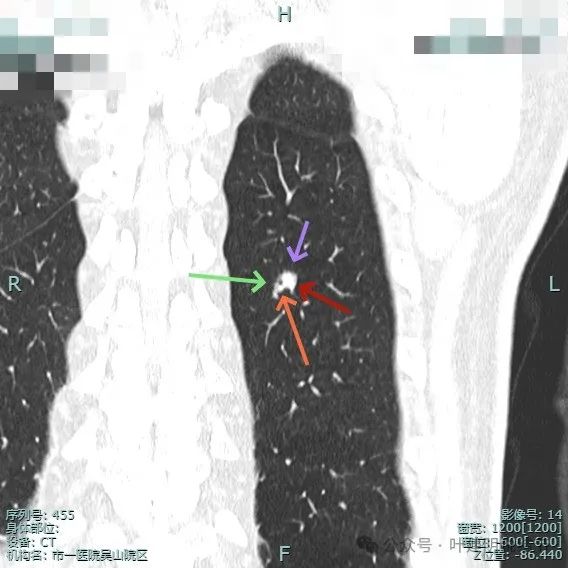

像个腰子的形态,靠下侧深凹进去,说明有收缩力吗?还是月牙铲征?

病灶表面细锯齿状,整体膨胀性明显,血管进入并异常增粗,整体轮廓清,周围肺野清晰。

病灶表面不平,形态略不规则,血管进入,边缘细锯齿状。

进入的血管壁显得毛糙,有异常增粗,结节与邻近血管之间有间隙征,整体有膨胀感。